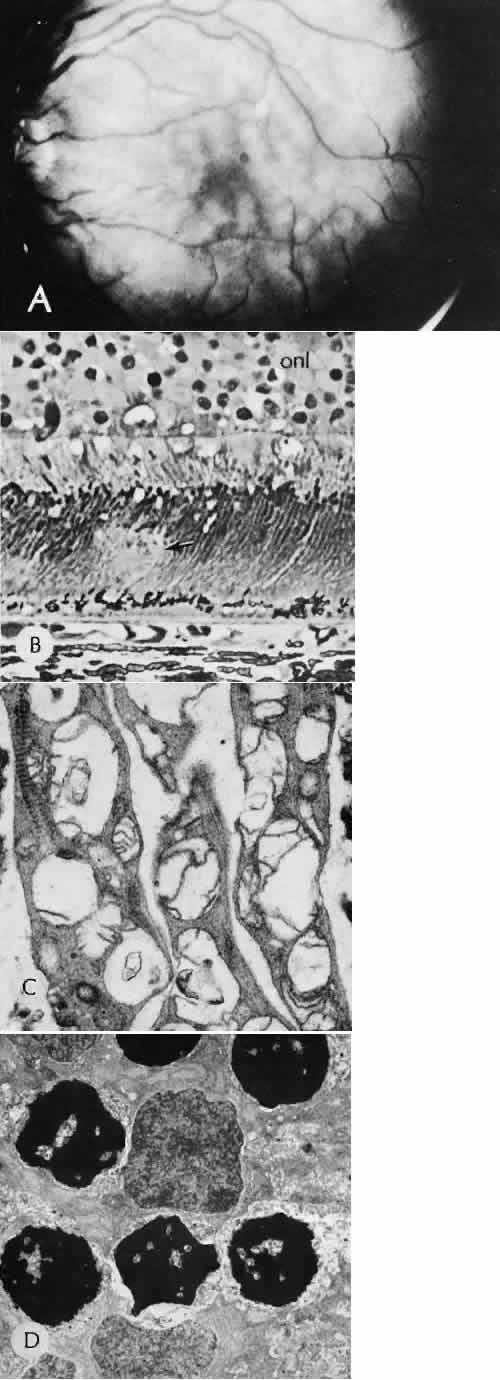

Fig. 20. Cyclodiathermy treatment of the ciliary body to control glaucoma. A. Gross photograph illustrates extensive areas of depigmentation mainly in the region of the pars plana (arrows) rather than the pars plicata. B. Light micrograph of the region of the pars plana illustrates an extensive area of tissue degeneration of the pars plana (between arrows) in the late postoperative course. C. Light micrograph of the destructive effects of cyclocryotherapy also in the region of the pars plana and pars plicata. The ciliary epithelium in the early postoperative period is necrotic and cystic. (Hematoxin-eosin stain; A, × 8; B, × 16.)